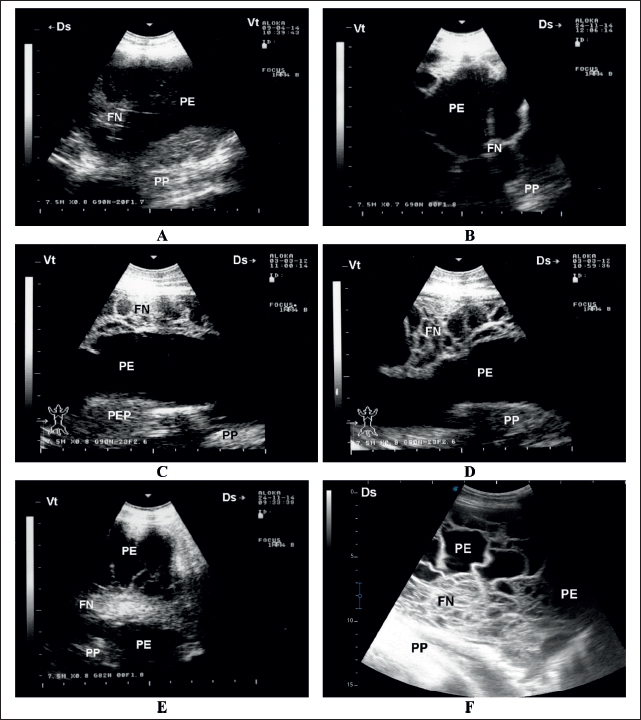

In diseased sheep, ultrasonography of the lungs revealed a consolidated pulmonary parenchyma resembling hepatic texture; the lesions were visualized unilaterally in 28 cases and bilaterally in 6 cases. Pleural effusions were the outstanding sonographic findings in all diseased animals. The echogenicity of the pleural fluid ranged from anechoic to hyperechoic, with imaging showing precipitates in the pleural effusion. Fibrin networks were also visualized in 27 animals that were either mild or massive (Fig. 2). Dyspnea symptoms improved in sheep following pleural effusion aspiration. The volume of aspirated pleural fluid was 50–800 ml (Fig. 3). No other sonographic findings were detected in the abdominal cavity. In control sheep, no sonographic abnormalities were detected on thoracic or abdominal imaging.

Fig. 2. Sonographic findings in six sheep with contagious caprine pleuropneumonia. Images A and B show PE , mild FN, and compressed PP. Image C shows moderate FN in the absence of PEP. Images D–F show a massive FN in three animals. FN=fibrin network; PE=pleural effusion; PEP=pleural effusion precipitate; PP=pulmonary parenchyma.